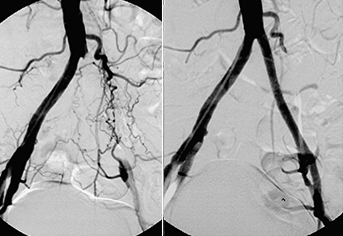

Renovascular Hypertension – is suspected in patients with high blood pressure that is difficult to control or that requires more than 3 drugs and may be associated with worsening of kidney function or kidney failure.